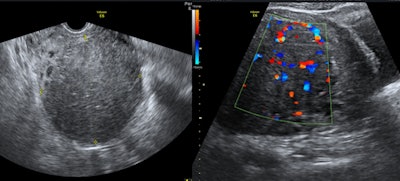

خلال عملية معالجة الورم الليفي الرحمي بالقثطرة.

تتميز معالجة الأورام الليفية الرحمية عن طريق القثطرة بأنها أبسط و بأن نسبة المشاكل والاختلاطات أقل مقارنة بالاستئصال الجراحي حيث يتم اجراء القسطرة بدون تخدير عام و ياخذ الاجراء 45 دقيقة و تخرج المريضة من المشفى في نفس اليوم.